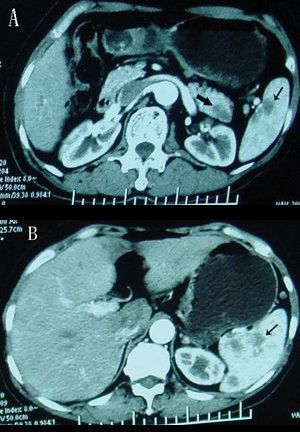

CT scans of the pancreas demonstrating a mass in the pancreatic tail and metastases in the spleen; source: Rong Y, Lou W, Jin D, Wikimedia Commons